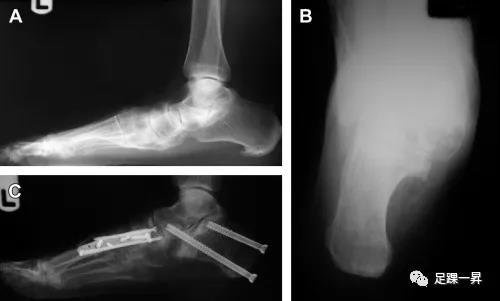

手术治疗:软组织手术主要包括肌腱修复、肌腱转位、三角韧带、弹簧韧带修复等;骨性手术包括跟骨内移截骨、外侧柱延长、关节制动术等。III期、IV期成人获得性扁平足手术治疗主要为三关节融合+截骨术。